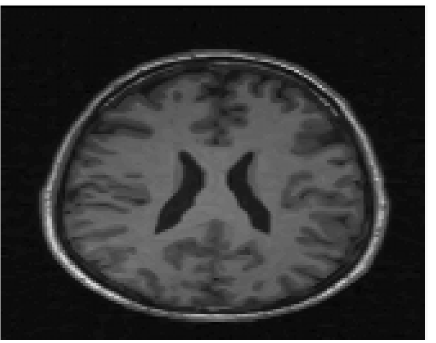

In this section we present some of the numerical results obtained with our method and compare it to other techniques. We compare the local version of our method to standard CS recovery algorithm (5) and to the edge-guided CS proposed in [25]. The non local version of our model is compared to the non local CS recovery (29), which does not take into account the geometric information of the non local gradients into the recovery process. For the non local case, in our model we have regularized the divergence of the normal with the standard ROF model.

We use partial Fourier measurements for our reconstruction and perform radial sampling on R𝑅R with different number of measurements in relation to the size of the signal (we specify it with the ratio mn𝑚𝑛\frac{m}{n}). For a fair comparison, we have used the same robust edge detector (9) for the edge-guided CS and our method and we have implemented the minimizations with the same splitting and augmented Lagrangian techniques for all the methods. The parameter α𝛼\alpha, which is related to the noise present in the CS measurements, has been manually tuned to obtain best reconstruction with the standard CS recovery models (5) and (29) and used with the other methods. The other parameters of our model γ,μ𝛾𝜇\gamma,\mu have also been chosen manually to obtain good CS recovery in terms of SNR. We have observed that γ𝛾\gamma (which controls the weight given to the alignment of the normals) takes similar values for the same kind of images (textured or brain IRM images) and remains stable for different sparsity and noise levels. On the other hand, the parameter μ𝜇\mu controlling the smoothness of the estimated normals decreases when the number of measurements decreases or the noise level increases because the partial reconstructions and the estimated normals are noisier and require more regularization.